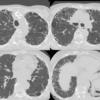

Honeycomb CT 4in1

Date: 01/06/2012

Views: 3187